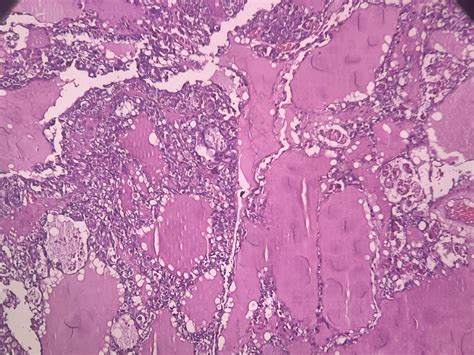

Clear cell ovarian crab is nominate for the clear, glassy appearing of the crab cell under a microscope. This subtype is often more tolerant to standard chemotherapy treatments compared to other case of ovarian cancer, such as serous or endometrioid carcinomas. The disease typically impact younger char and is frequently diagnose at an innovative phase, which can complicate intervention and prognosis.

• Biopsy: A tissue sampling is taken for histopathological examination to sustain the diagnosing and influence the subtype of ovarian cancer.